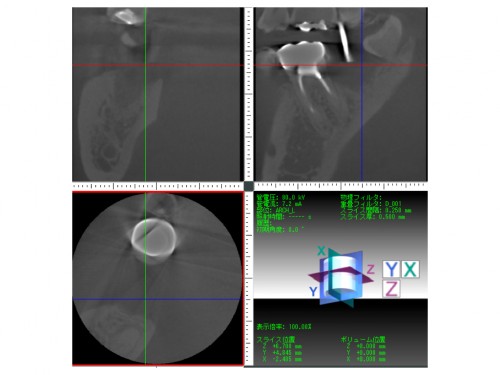

インプラント治療を行う際はレントゲンCTが必須です。

CTでインプラントの入る骨の厚みがあるのか調べます。

レントゲンCTを分析し、インプラント治療を行う位置を決めていきます。

その通りの位置にインプラント治療を行います。

位置がずれていたりすると見た目もおかしな歯になってしまいます。